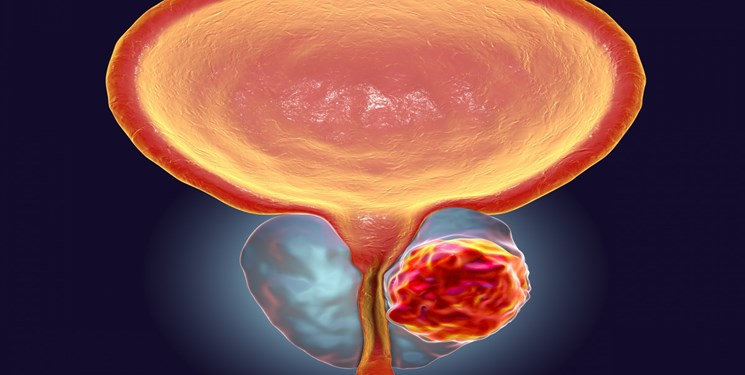

به گزارش بهداشت نیوز٬ فوق تخصص اندویورولوژی در چهاردهمین کنگره بینالمللی انجمن اندویورولوژی و یورولاپاراسکوپی ایران در خصوص بیماریهای مرتبط با پروستات و شیوع آن در بین مردان٬ گفت: این غده در مردان بعد از مثانه قرار دارد و اصولاً با افزایش سن دچار تغییرات زیادی میشود و این تغییرات با افزایش فشار در داخل مجرای ادراری در دفع ادرار اختلال ایجاد میکنند و مجموعه این تغییرات بزرگی خوشخیم پروستات نام میگیرد.

وی با اشاره به اینکه افزایش سایز پروستات از 30 سالگی آغاز میشود٬ گفت: با افزایش سن علائم ادراری بیمار آغاز و به تدریج افزایش پیدا میکند؛ به گونهای که افراد در 40 سالگی در کمتر از 8 درصد موارد اما در یک فرد 80 ساله با شیوع بسیار بیشتر٬ علائم شدیدتری را تجربه میکنند.

طبیبی ادامه داد: علائم این بیماری به صورت خفیف تا شدید میتواند در بیمار ظاهر شود. تکرر ادرار در روز و شب، سوزش ادرار، احساس سریع برای تخلیه ادرار و در نهایت اشکال در تخلیه و قطع و وصل شدن ادرار از مهمترین علائم این بیماری به شمار میروند.